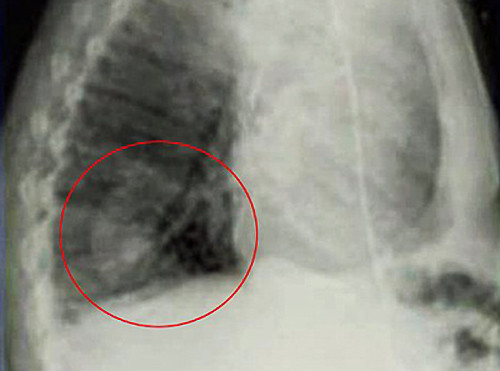

Vào năm 2009, khi mổ cắt u phổi cho một nam bệnh nhân, các bác sĩ Nga phát hiện một cây linh sam cao khoảng 5 cm mọc trong phổi, và đây chính là tác nhân khiến họ tưởng bệnh nhân bị ung thư, với triệu chứng đau dữ dội ở ngực và ho ra máu.

Các bác sĩ đoán rằng có thể trước đó bệnh nhân đã hít phải một hạt linh sam, hạt này nảy mầm và mọc thành một cây nhỏ trong phổi.